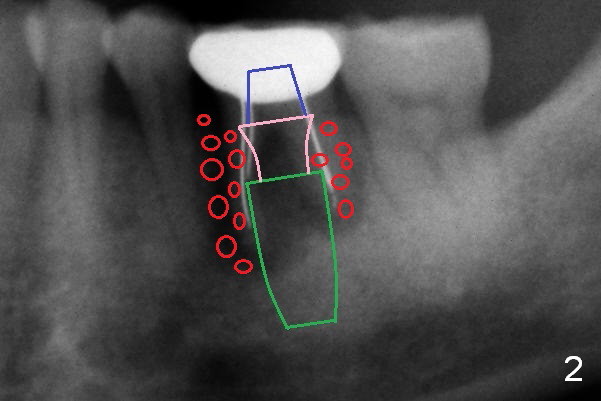

A 50-year-old man (CZ) requests implant restoration at the tooth #19 (Fig.1). After Metronidazole, a large (5 mm and up) immediate implant is going to be placed deep (Fig.2 green) with an abutment (blue) with long cuff (3 or 4 mm, pink). A large amount of bone graft (red) placed around the implant and against the distal root surface of #20. Osteotomy is initiated in the septum. If the height of the latter is more than 7 mm (take preop PA), set stopper at 7 mm (shortest). Otherwise open Magic Sinus Kit or Sinus Master Kit (shortest stopper 1 and 2 mm, respectively). Also take preop photos to show whether there is buccal or lingual gingival recession. Two dummy implants (5x9, 5x11 mm) will try in. If they are placed too deep, more than 4 mm from the gingival margin, switch to UF or SM. The cemented abutment's cuffs are longer, 5 or 6 mm.